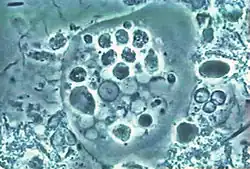

| Entamoeba gingivalis from periodontal pocket [1] | |

It is found in the mouth[5] inside the gingival pocket biofilm near the base of the teeth, and in periodontal pockets.[1] Entamoeba gingivalis is found in 95% of people with gum disease and rarely in people with healthy gums.[6][7] Cyst formation is not present; therefore transmission is direct from one person to another by kissing, or by sharing eating utensils. Only the trophozoites are formed and the size is usually 20 micrometers to 150 micrometers in diameter. Entamoeba gingivalis have pseudopodia that allow them to move quickly and phagocytise the nucleus of polynuclear neutrophils by exonucleophagy in periodontal disease.[8] Their spheroid nucleus is 2 micrometers to 4 micrometers in diameter and contains a small central endosome. There are numerous food vacuoles, which consists mostly of phagocytised PMN nucleus, blood cells, and bacteria. It also causes pyorrhoea.

Media